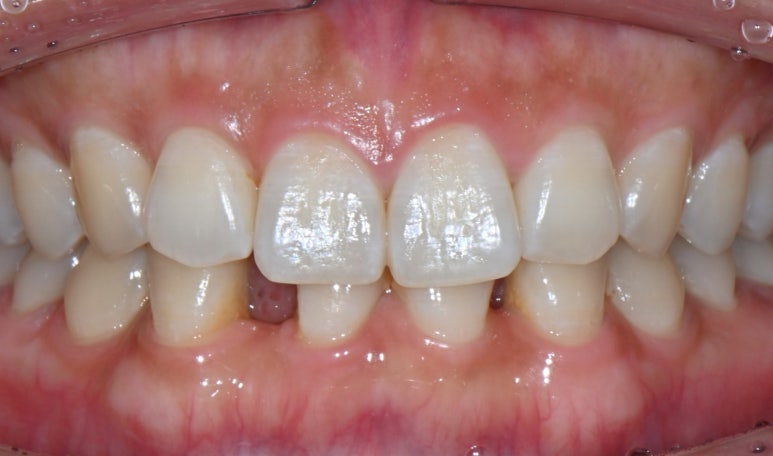

오늘은 하악 앞니 2개가 모두 결손되어

평생 고민이 많으셨던 여성 환자분의

'치아 삭제 최소화' 브릿지 치료 사례를 소개해 드립니다.

26.03.12 아래앞니 공간